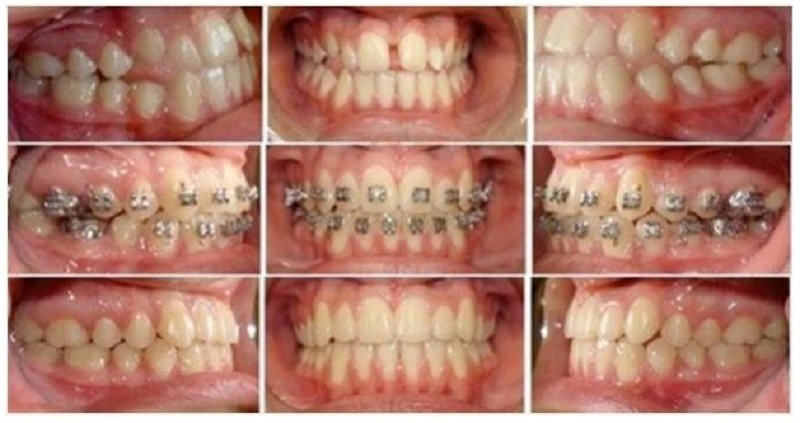

2. Trình tự thay dây theo giai đoạn.

2.1. Giai đoạn làm thẳng (alignment) và làm phẳng cung răng.

Sau khi gắn band và mắc cài, dây cung sơ khởi sẽ được buộc vào mắc cài. Bất cứ sự chuyển dạng nào của dây cung này cũng gây ra lực đặt lên răng, hoạt hóa cơ chế sinh học của di chuyển răng. Nếu chỉ có mắc cài và band thì không thể di chuyển răng được. Răng di chuyển để đáp ứng với lực áp dụng, và dây cung là phương pháp tiện dụng để áp dụng lực này.

Dây cung sơ khởi sẽ luôn luôn là dây cung Niti. Các dây này có TRÍ NHỚ để khi dây cung bị bóp méo khỏi hình dạng ban đầu, nó sẽ muốn quay lại hình dạng nguyên thủy của mình. Dây cung sẽ phải vặn xoắn khi buộc chúng vào mắc cài của các răng lệch lạc, tạo nên lực trên dây chằng nha chu vì dây cung muốn trở lại hình dạng ban đầu. Lực xoắn vặn, hợp kim làm dây cung và nhiệt hóa dây cung, và kích thước dây cung sẽ xác định mức độ lực đặt lên răng.

Ta nhận thấy rằng lực giải phóng từ dây cung 012N (Niti) nhỏ hơn so với dây 014N, và dây 014N lại nhỏ hơn dây 016N do lượng xoắn vặn. Dây cung sơ khởi được chọn dựa trên lượng chen chúc nhiều hay ít và khả năng chịu đựng của bệnh nhân. Thường sẽ có phản ứng đau nếu chúng ta áp dụng lực quá lớn lên mô nha chu để làm di chuyển răng trong giới hạn sinh học. Tuần hoàn tại mô nha chu bị ngắt, ngăn hoạt động tế bào của hủy cốt bào và tạo cốt bào.

Do đó, nên dùng dây 012N với những răng xoay nặng hoặc ở bệnh nhân người lớn nhạy cảm. Có thể duy trì dây 012N trong 2-3 tháng không cần hoạt hóa lại. Nếu không thấy răng thẳng hàng toàn bộ, thì cần thay dây Niti khác phụ thuộc vào độ lệch lạc còn lại trên cung hàm. Có thể dùng dây 012N và 014N không cần chú ý đến hình dạng vì nó không ảnh hưởng đến hình dạng cung răng. Những dây cung này chỉ được dùng để căn thẳng các mắc cài.

Dùng dây 014N khởi đầu trong các trường hợp không có chen chúc nặng. Dây cung này có thể được duy trì trong miệng không biến dạng trong vòng 4-5 tháng, và đôi khi chỉ cần dùng một dây này để hoàn thành giai đoạn làm thẳng. Cần để ý đến sự biến dạng của dây cung nếu dây cung được buộc vào các răng xoay mà không thể uốn và trở lại hình dạng ban đầu của nó.

2.2. Buộc dây cung hoàn toàn.

(dây cung nằm thụ động trong khe mắc cài)

Tiến hành làm thẳng mắc cài cho đến khi mắc cài được buộc hoàn toàn:

Mục tiêu của giai đoạn làm thẳng là để dây cung nằm thụ động trong khe mắc cài. Mắc cài đặt trên răng ở vị trí tiêu chuẩn, và sau đó buộc dây cung Niti cho đến khi nó nằm THỤ ĐỘNG trong khe mắc cài. Khi dây đã nằm ở vị trí thụ động tại mỗi mắc cài thì có thể buộc dây cung vào khe mắc cài bằng chun tại chỗ. Nếu dây cung chưa nằm thụ động (ví dụ: bạn phải ấn dây vào khe mắc cài và khi giải phóng áp lực đó thì dây có thể bị bung ra), thì cần buộc bằng dây thép (ligature). Ligature thép sẽ giữ dây cung niti trong giai đoạn chưa thụ động này cho đến khi có thể buộc dây vào mắc cài hoàn toàn.

Khi dây cung Niti trở nên thụ động trong tất cả các khe mắc cài ở cả hai dây cung, thì bạn sẽ phải xác định lại xem mắc cài đó được gắn đúng chỗ hay không. Nếu mắc cài đã được gắn đúng, thì không còn răng nào bị xoay nữa. Nếu mắc cài nào bị gắn sai chỗ thì cần phải gắn lại để chỉnh lại xoay sai hoặc góc sai. Góc mắc cài bị sai được định giá bằng phim Panorama tiến trình, hoặc mẫu nghiên cứu tiến trình. Sai sót về chiều cao một răng nào đó có thể không cần phải gắn lại, vì những sai sót này sẽ được sửa dễ dàng trong giai đoạn hoàn tất.

2.3 Dây cung và giai đoạn dây cung cứng (wire progression).

Sau giai đoạn làm thẳng, sẽ bắt đầu giai đoạn dây cung cứng với mục đích là đặt được dây cung thép chữ nhật vào hai cung hàm. Dây cung thép (SS), thường sử dụng dây 19X25 là chủ yếu, cho các mục đích sau: